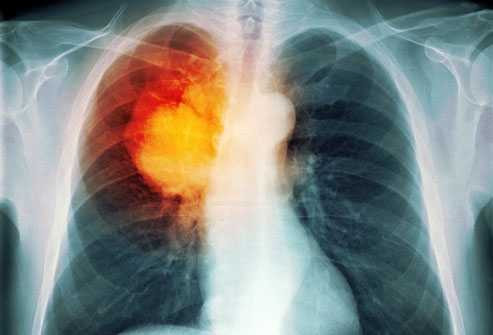

Ung thư phổi là căn bệnh nguy hiểm có tỷ lệ tử vong cao nhất trong các loại bệnh ung thư; theo các nhà khoa học và chuyên gia y tế, thuốc lá là nguyên nhân hàng đầu gây nên căn bệnh đáng sợ này.